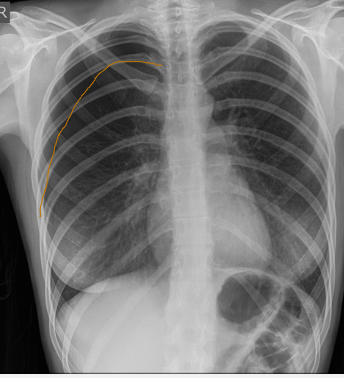

What does this CXR indicate? - Pneumoperitoneum - Pneumothorax - Pulmonary oedema - Consolidation - Pleural effusion

What does this CXR indicate? - Pneumoperitoneum - Pneumothorax - Pulmonary oedema - Consolidation **Pleural effusion: blunted costophrenic edges**